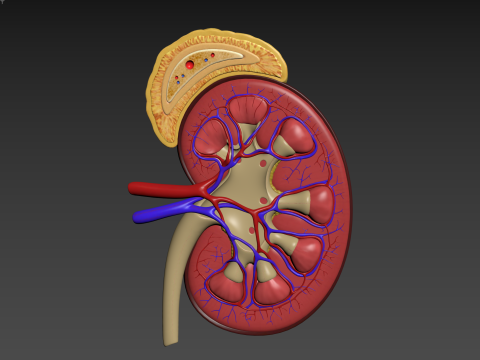

Human Kidney Low-poly Modelo 3D

Human Kidney Modelo 3D blend, jpg, fbx, max, De jack2024

human kidney renal urine organ anatomical health people anatomy biology urinary system electrolytes internal organs science medical crossNo hay comentarios sobre este artículo.